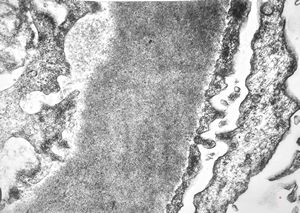

F,14y. | Alport syndrome - split and laminated, thick/thin basement membranes